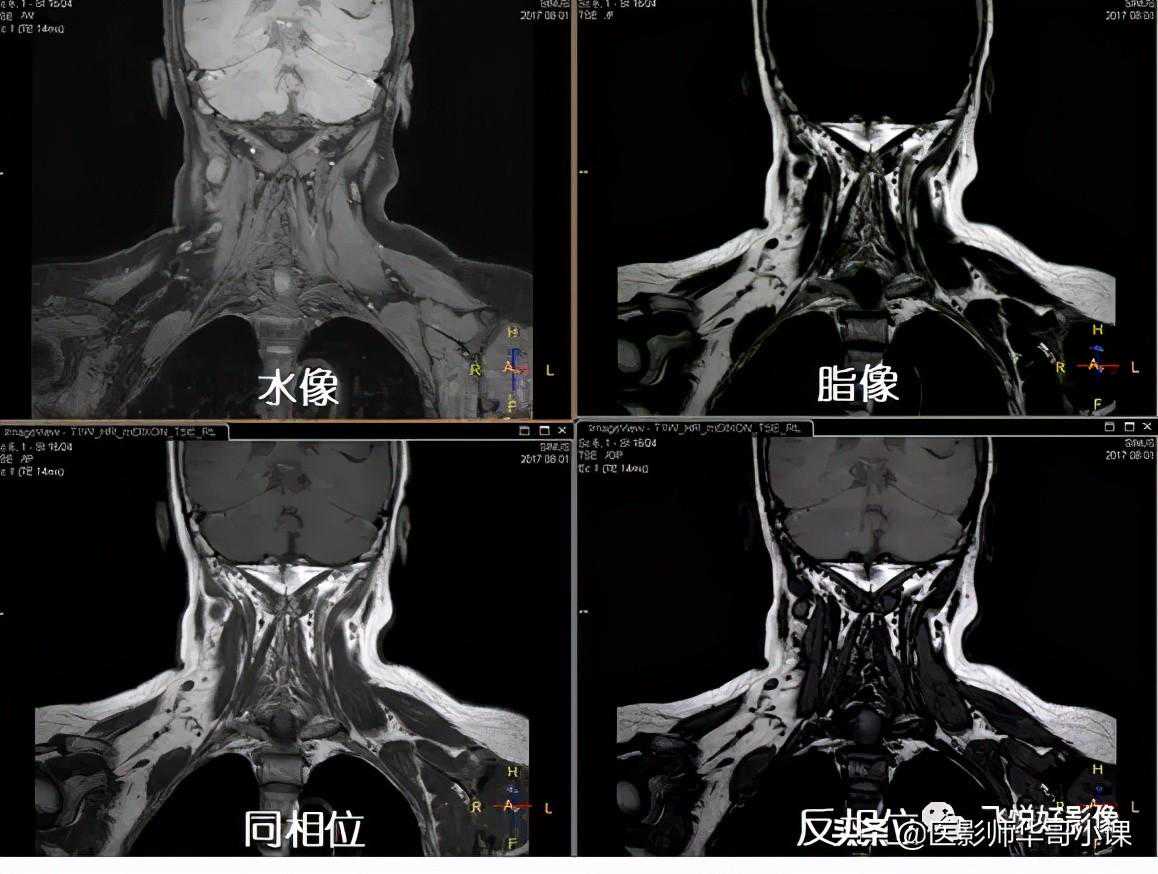

一次成像,四种组织对比度

在颈部扫描中,脂肪抑制一直是难点,上图中右侧一组图像是T1W_SPIR,看到脂肪抑制不均匀,仍残留部分脂肪信号。左侧一组图像是mDIXON_XDTSE,脂肪抑制均匀,更好的显示组织对比。

在颈椎扫描中,使用三种脂肪抑制技术进行成像,SPIR脂肪抑制不均匀,STIR脂肪抑制均匀,但SNR较低,mDIXON既能均匀抑制,也能保留良好的SNR。